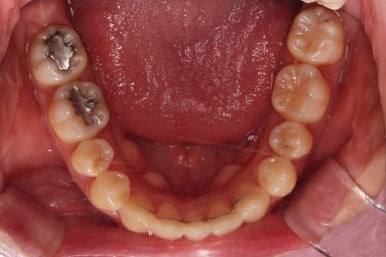

중앙선, 교합, 앞니 맞물림 등 모든 것이 좋아졌네요.

교합, 정중선 모두 좋아졌고요.

웃을 때 한 쪽으로 쏠려있던 중앙도 개선되어 예뻐졌고, 치아 높낮이도 조절하여 웃을 때 보이는 앞니의 길이도 매우 예븐 정도로 조절이 되었습니다.

이상 아래 앞니를 뽑고 교합과 정중선, 돌출감이 애매했던 환자분이 부산재교정 치료했던 사례였습니다.